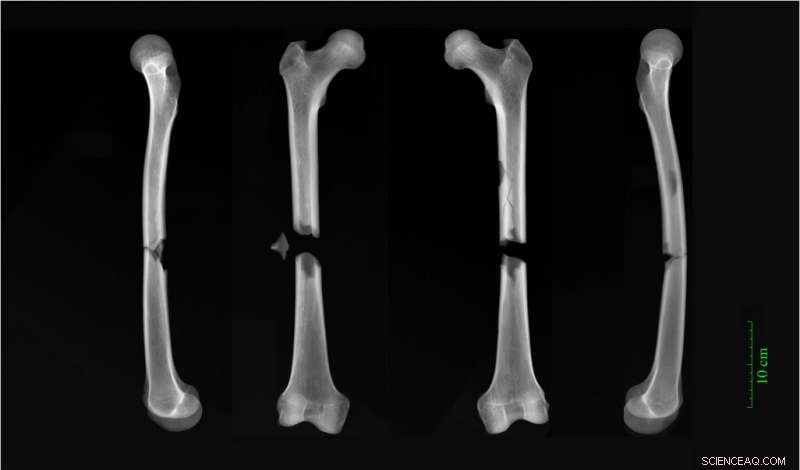

"The friar had complete fractures halfway up both his femurs," said Dittmar. The femur [thigh bone] is the largest bone in the body. "Whatever caused both bones to break in this way must have been traumatic, and was possibly the cause of death."

Dittmar points out that today's clinicians would be familiar with such injuries from those hit by automobiles—it's the right height. "Our best guess is a cart accident. Perhaps a horse got spooked and he was struck by the wagon."

X-rays of butterfly fractures to both femora of an adult male buried in the Augustinian friary. Credit: Dr Jenna Dittmar